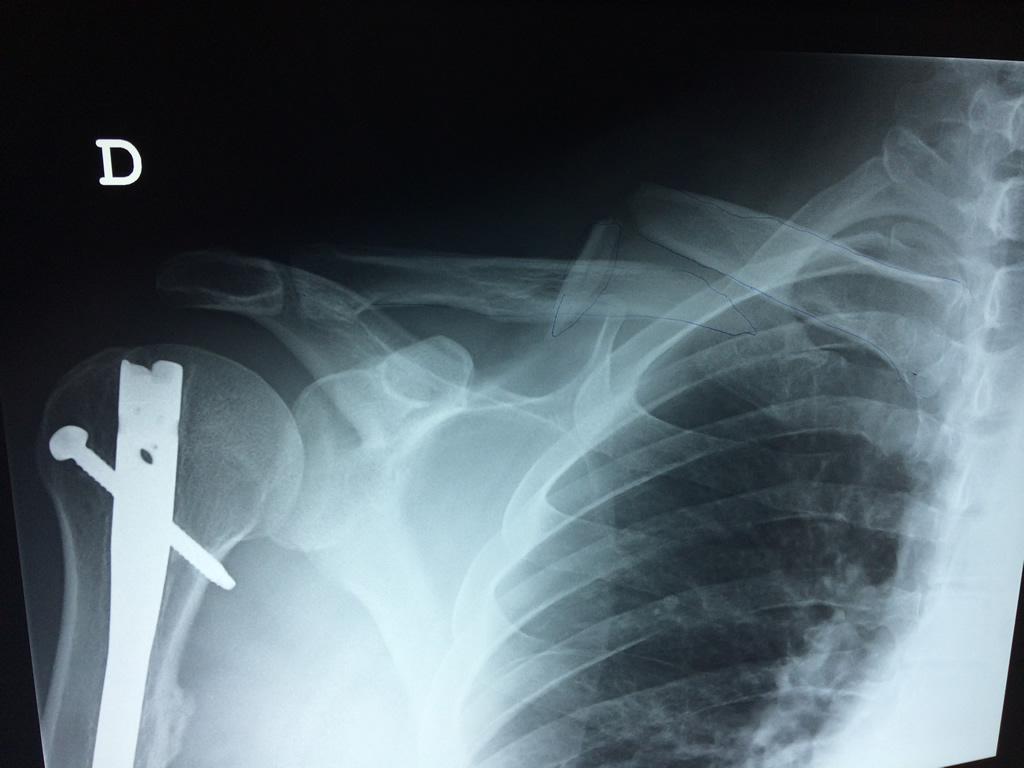

Húmero - Clavícula

La clavícula es un hueso largo, con forma de "S" itálica, situado en la parte anterosuperior del tórax. Junto con la escápula forman la cintura escapular. Se puede palpar por toda su longitud y se extiende del esternón al acromion de la escápula, siguiendo una dirección oblicua lateral y posterior.

Se considera el único medio de unión entre el miembro superior y el tórax. A pesar de su aspecto, similar al de un hueso largo, posee una estructura semejante a la de un hueso plano, ya que carece de epífisis y de diáfisis, lo que la harían entrar dentro de la clasificación de hueso largo. Carece de un canal medular propiamente dicho.